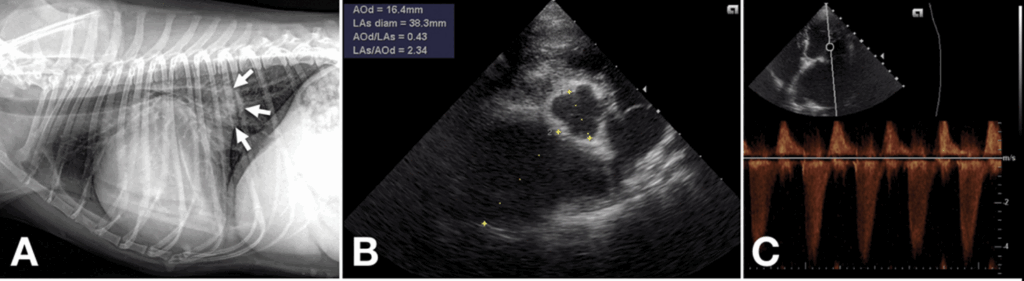

Fig 5. A: 부분 심낭절제술 1개월 후 촬영한 흉부 방사선 사진입니다. 점액종성 승모판 변성(myxomatous mitral valve degeneration)에 특징적인 좌심방 확장을 동반한 심한 심장비대(흰색 화살표)가 관찰되지만, 폐 침윤 소견은 보이지 않습니다.

B: 부분 심낭절제술 1개월 후 시행한 심장초음파 검사에서 좌심방/대동맥 비율이 2.34로 측정되었으며, 이는 좌심방이 심하게 확장되었음을 의미합니다.

C: 좌측 흉골 옆 단면에서 심실 수축기 동안 심실에서 심방으로 4 m/s 이상의 승모판 역류가 관찰됩니다.

(A: Radiography of the present patient 1 month after partial pericardiectomy shows severe cardiomegaly with left atrial enlargement (white arrows), which is characteristic of myxomatous mitral valve degeneration, but pulmonary infiltration is not observed.

B: Echocardiography of the present patient 1 month after partial pericardiectomy shows a left atrial/aortic root ratio of 2.34, which implies severe enlargement of the left atrium.

C: The left parasternal view shows mitral regurgitation > 4 m/s from the ventricle to the atrium during ventricular systole.)